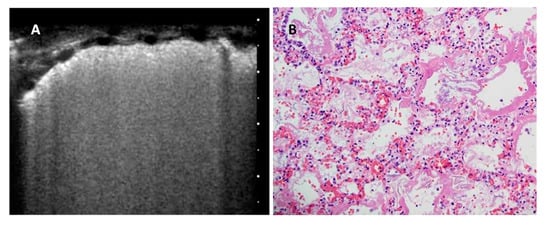

A-Lines is a generic term indicating horizontal artifacts related to a normal lung surface. In this review, we consider these artifacts as the summation of the reverberation effects, due to the pleural-line and myofascial acoustic interfaces of the chest wall, and the mirror effects (variable in its expression in relation to the thickness of the chest wall) reproducing beyond the pleural line, in a specular way, the myofascial planes of the chest wall (Figure 1).

Normal pleural line. (Left): Healthy subject, B Mode image. The pleural line is regular, below the pleural line, the image does not represent the anatomy of the lung. (Right): Below the echogenic pleural surface the replica effects of the pleural line can be seen. In the box C, the replica of the contents of box A and the mirror effect of the contents of the box B are added together. (Images obtained with a commercially available machine, Toshiba Aplio XV, equipped with a linear probe, 9 MHz, without harmonic imaging).

Considering this kind of cortical lung porosity, the ultrasound pulse that hits a smooth visceral pleura, is reflected almost completely. Once the reflected echo has reached the probe, it can have enough energy to be partially back-reflected and reach the pleural-line again. In this case, the probe receives two echoes coming from the pleural-line. Consequently, with the transformation of the signal from the time domain to the space domain, the obtained spatial function shows two pleural-lines: the first is the real one and the second is an artifactual line, localized at a double distance (Figure 1).

This process can also generate more than two pleural-lines (replica effects) [28]. These lines, in the case of a healthy pleura, are regular, bright, and relatively thin. In literature, these horizontal artifacts are named A-Lines. We prefer to identify these artifacts, together with every sub-pleural mirror and replica effects of the chest wall tissues, as specular artifacts. In general, they indicate a healthy pleural surface [4].